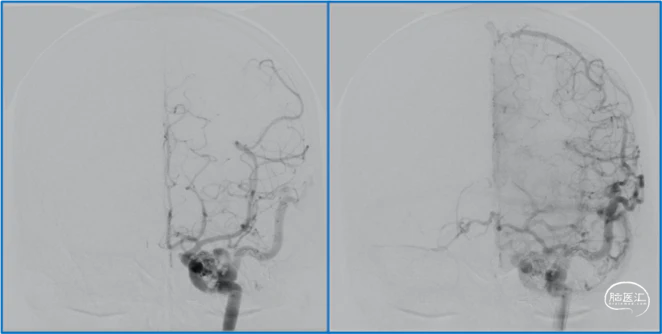

典型病例

蝶顶窦旁DAVF,可吸引前和中颅窝硬膜的所有动脉参与供血。其中颈内动脉及其分支的供血可以使用显微外科技术阻断;颈外动脉的供血动脉可以使用介入栓塞技术阻断。

介入栓塞眼动脉供血的要点:超选左侧眼动脉,跃过视网膜中央动脉,栓塞脑膜回返动脉对DAVF的供血。目的:保护眼动脉视网膜中央动脉分支,避免后期栓塞颈外动脉的供血动脉时损伤眼动脉。

稳妥的外科治疗方案:先介入栓塞颈外动脉的供血动脉,然后显微手术切断颈内动脉的供血动脉,阻断引流静脉,电凝封闭硬膜瘘口。